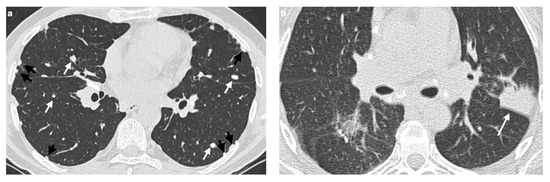

High-Resolution CT Findings in Interstitial Lung Disease Associated with Connective Tissue Diseases: Differentiating Patterns for Clinical Practice—A Systematic Review with Meta-Analysis

Objectives: Connective tissue diseases (CTDs) include a diverse group of systemic autoimmune conditions, among which interstitial lung disease (ILD) is acknowledged as a major determinant of prognosis. High-resolution computed tomography (HRCT) is the gold standard for ILD assessment. The distribution of HRCT patterns across CTDs remain incompletely defined. The objective of this systematic review is to synthesize available evidence regarding the prevalence of specific radiological patterns within CTD-ILDs and to assess whether specific patterns occur at different frequencies among individual CTDs. Methods: The inclusion criteria encompassed original human studies published in English between 2015 and 2024, involving adult participants (≥18 years) with CTD-ILDs assessed primarily by HRCT and designed as retrospective, prospective, or cross-sectional trials with extractable data. We systematically searched PubMed, Scopus, and Web of Science (January 2025). Risk of bias was evaluated using the Newcastle–Ottawa Scale (NOS) for cohort and case–control studies, and the JBI Critical Appraisal Checklist for cross-sectional studies. Data were extracted and categorized by HRCT pattern for each CTD, and then summarized descriptively and statistically. Results: We analyzed 23 studies published between 2015 and 2024, which included 2020 patients with CTD-ILDs. The analysis revealed non-specific interstitial pneumonia (NSIP) as the most prevalent pattern overall (36.5%), followed by definite usual interstitial pneumonia (UIP) (24.8%), organizing pneumonia (OP) (9.8%) and lymphoid interstitial pneumonia (LIP) (1.25%). HRCT distribution varied by CTD: NSIP predominated in systemic sclerosis, idiopathic inflammatory myopathies, and mixed connective tissue disease; UIP was most frequent in rheumatoid arthritis; LIP was more common in Sjögren’s syndrome. While global differences were statistically significant, pairwise comparisons often lacked significance, likely due to sample size constraints. Discussion: Limitations include varying risk of bias across study designs, heterogeneity in HRCT reporting, small sample sizes, and inconsistent follow-up, which may reduce precision and generalizability. In addition to the quantitative synthesis, this review offers a detailed description of each radiologic pattern mentioned above, illustrated by representative examples to support the recognition in clinical settings. Furthermore, it includes a brief overview of the major CTDs associated with ILD, summarizing their epidemiological data, risk factors for ILD and clinical presentation and diagnostic recommendations. Conclusions: NSIP emerged as the most common HRCT pattern across CTD-ILDs, with UIP predominating in RA. Although inter-disease differences were observed, statistical significance was limited, likely reflecting sample size constraints. These findings emphasize the diagnostic and prognostic relevance of HRCT pattern recognition and highlight the need for larger, standardized studies. Full article

Figure 1